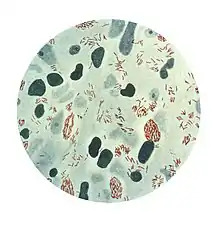

| Microphotograph of Mycobacterium leprae taken from a skin lesion. The small brick-red rod-shaped cells appear in clusters. Source: CDC | |

Mycobacterium leprae is an intracellular, pleomorphic, non-sporing, non-motile, acid-fast, pathogenic bacterium.[3] It is an aerobic bacillus (rod-shaped bacterium) with parallel sides and round ends, surrounded by the characteristic waxy coating of mycolic acid unique to mycobacteria. It is Gram-positive by Gram staining, but Mycobacterium leprae was traditionally stained with carbol fuchsin in the Ziehl–Neelsen stain. Because the bacilli are less acid-fast than Mycobacterium tuberculosis (MTB), the Fite-Faraco staining method, which has a lower acid concentration, is used now.[9][10] In size and shape, it closely resembles MTB. The bacteria are found in the granulomatous lesions and are especially numerous in the nodules. This bacteria often occur in large numbers within the lesions of lepromatous leprosy and are usually grouped together as a palisade.[6] By optical microscopy of host cells, Mycobacterium leprae can be found singly or in clumps referred to as "globi", the bacilli can be straight or slightly curved, with a length ranging from 1–8 μm and a diameter of 0.3 μm.[11] The bacteria grow best at 27 to 30 °C, making the skin, nasal mucosa and peripheral nerves primary targets for infection by Mycobacterium leprae.[12]